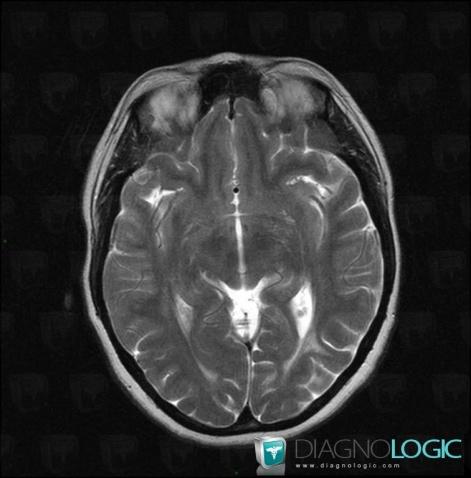

Progressive multifocal leukoencephalopathy, Cortico subcortical region, Cerebral hemispheres, MRI

Here is the specific information in the key image above:

- Diagnosis Progressive multifocal leukoencephalopathy, Location(s) Cerebral hemispheres, with gamuts Intracerebral T2W or FLAIR hyperintense lesion, White matter diseaseCortico subcortical region, with gamuts Subcortical lesion